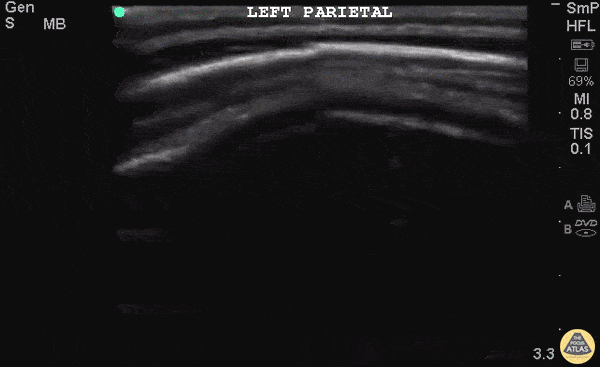

10 month old F presents one day after unwitnessed height level fall. Left parietal hematoma without step-off found on physical exam. Otherwise well appearing with normal vital signs. POCUS found a defect in cortex in area of the hematoma. CT head confirmed non-displaced skull fracture of the left parietal bone. Patient was observed and did not require neurosurgical intervention. More research is needed into the value of POCUS for pediatrics skull fractures and how it can fit into our PECARN decision rules. Dr Iain Jeffery - Brooklyn Hospital Emergency Medicine Dr. Tian Liang and Dr Jeffery Rallo - Kings County Department of Pediatrics Emergency Medicine